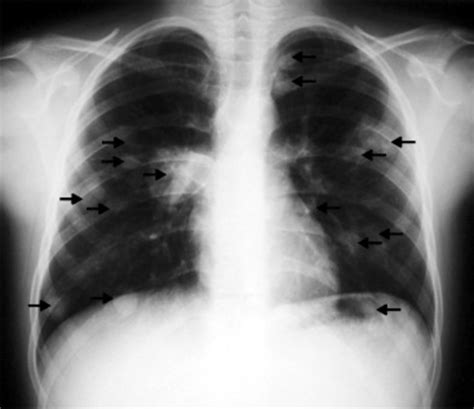

En un cuadro agudo, la inestabilidad hemodinámica puede presentarse en neumonía necrosante, embolismo séptico, aspergilosis pulmonar invasiva y mucormicosis, especialmente en pacientes con factores de riesgo como diabetes, abuso de alcohol, terapia con corticosteroides e inmunosupresión. La presencia de catéteres venosos centrales, marcapasos, válvulas protésicas cardiacas, o abuso de drogas intravenosas puede relacionarse con embolismo séptico, caracterizado por nódulos bilaterales periféricos en diferentes etapas de cavitación.

Un nódulo pulmonar solitario cavitado tiene una mayor probabilidad de ser maligno. El cáncer primario de pulmón se cavita en aproximadamente el 22% de las TAC, siendo más frecuente en el carcinoma de células escamosas. Las metástasis se cavitan con menos frecuencia (menos del 4%) y suelen aparecer en las bases pulmonares y subpleurales.